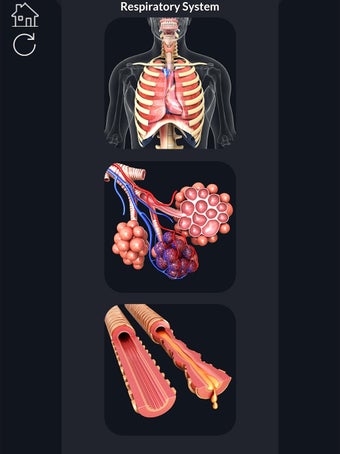

「Visual 3D Science」によるAndroid用の無料プログラムです。

このアプリケーションは、高度にリアルな呼吸器系のモデルです。ユーザーは任意の角度および任意の平面から呼吸器系の解剖学を表示できます。ユーザーは360°回転し、ズームインおよびズームアウトして解剖学をよりよく研究することができます。ユーザーはまた、画面に描画するためのさまざまなツールを使用して写真を撮ることもできます。